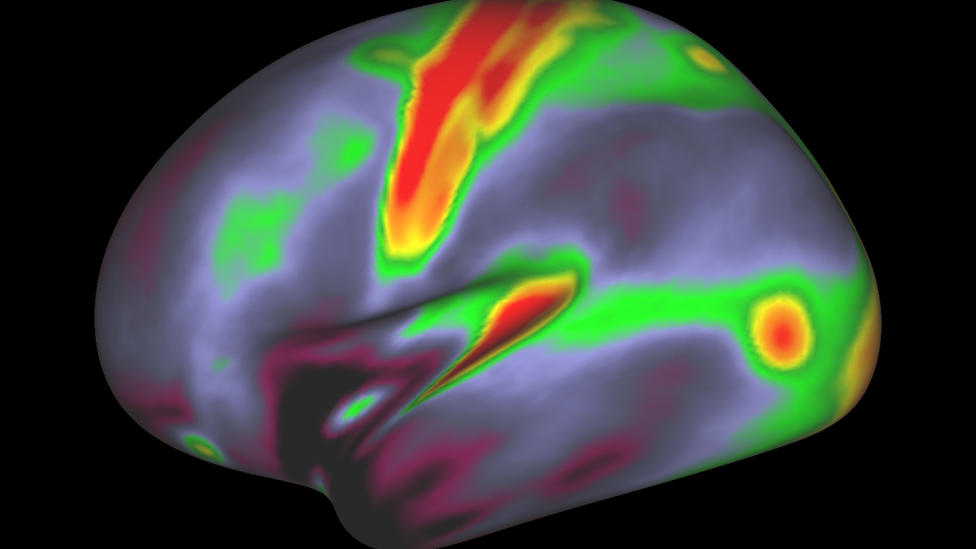

These are the areas that responsed to a language-based task (following a story)

The motor cortex (top centre), with its longer-reaching connections, contains more myelin